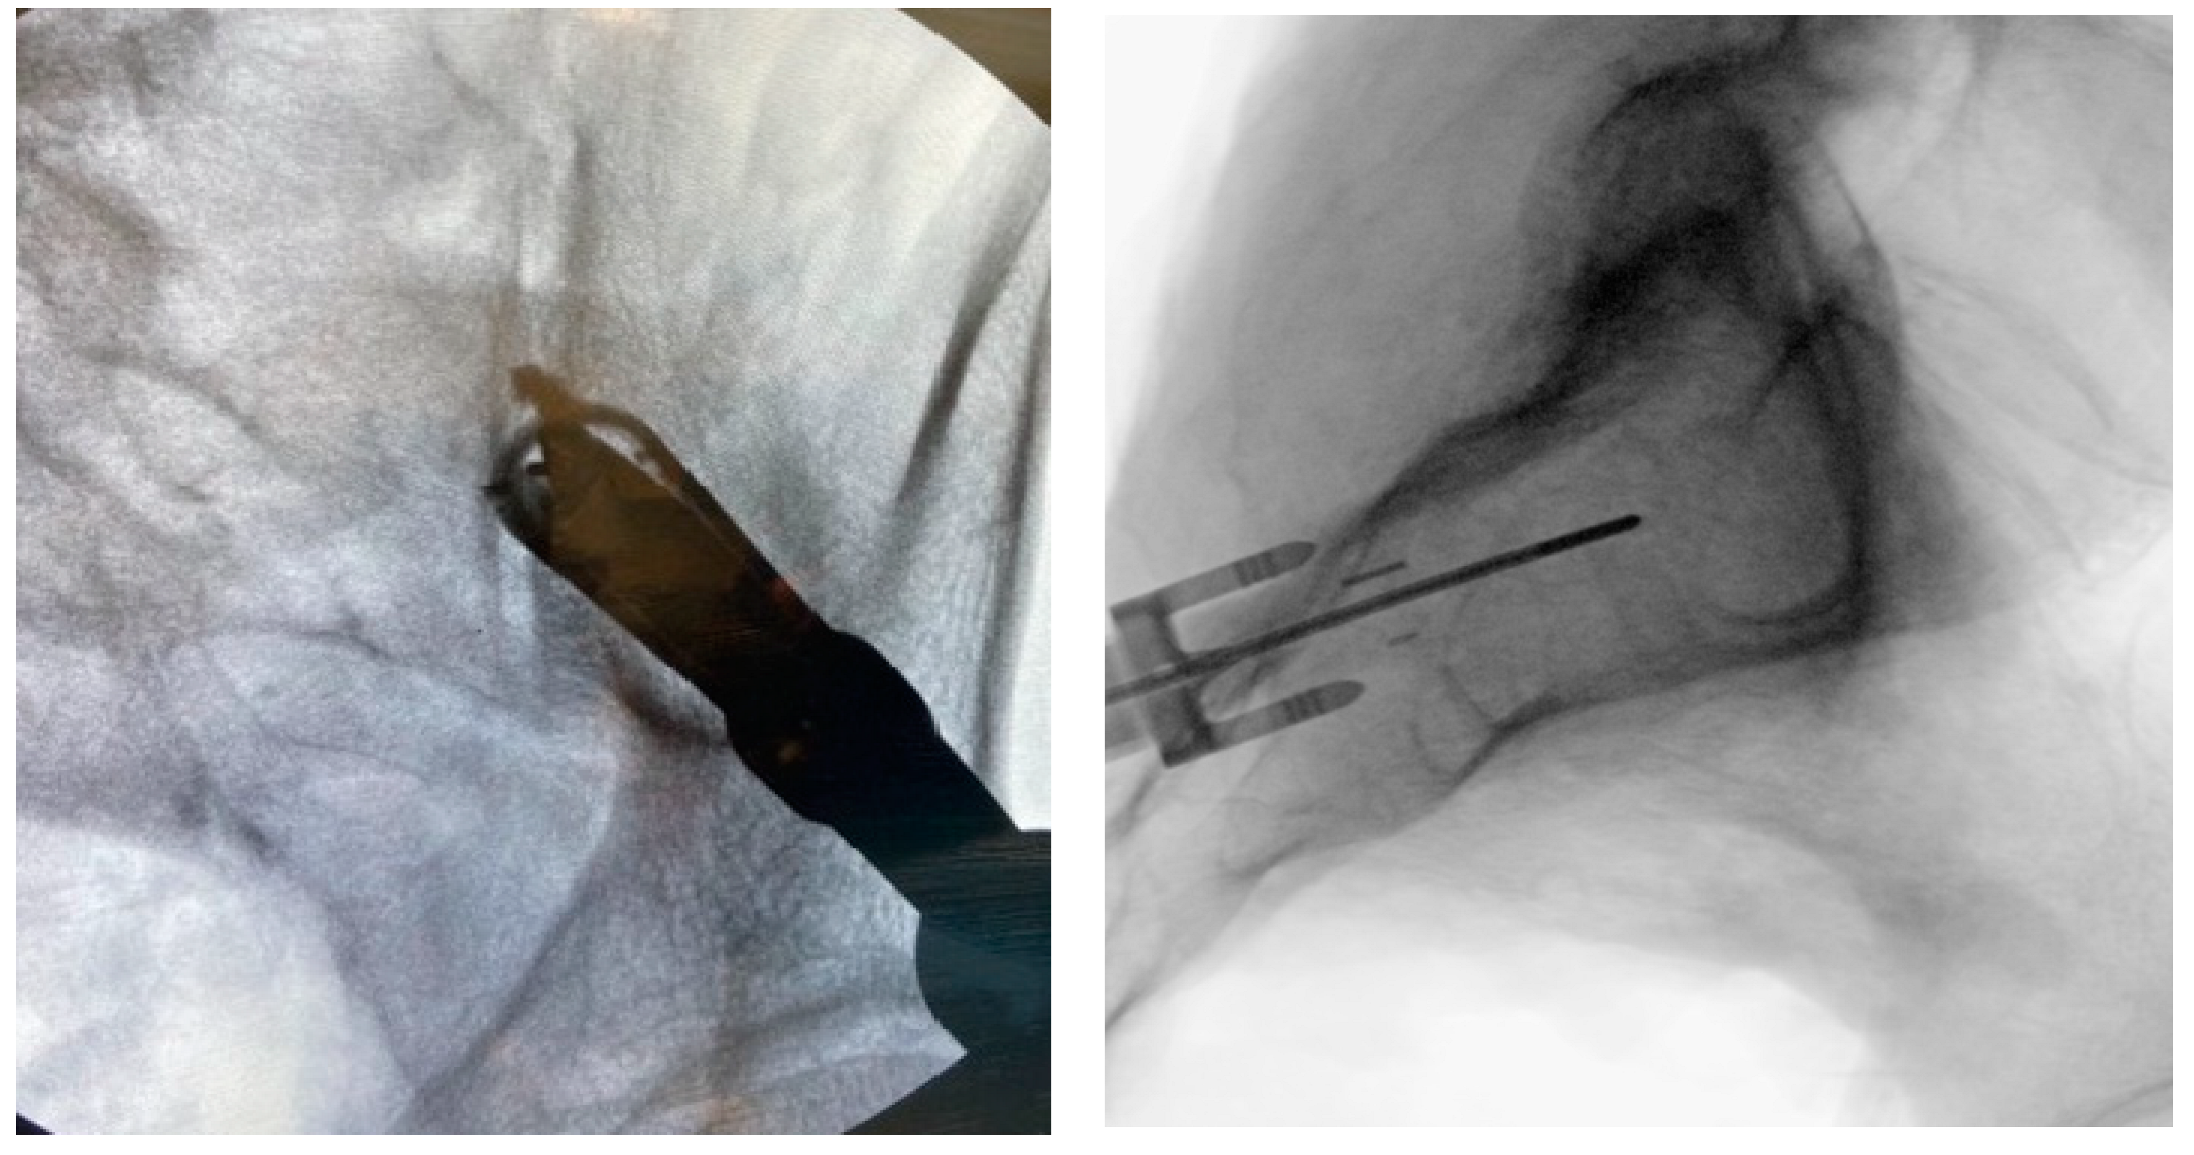

3.3.5. Tissue Dilation

3.3.6. Implant Preparation